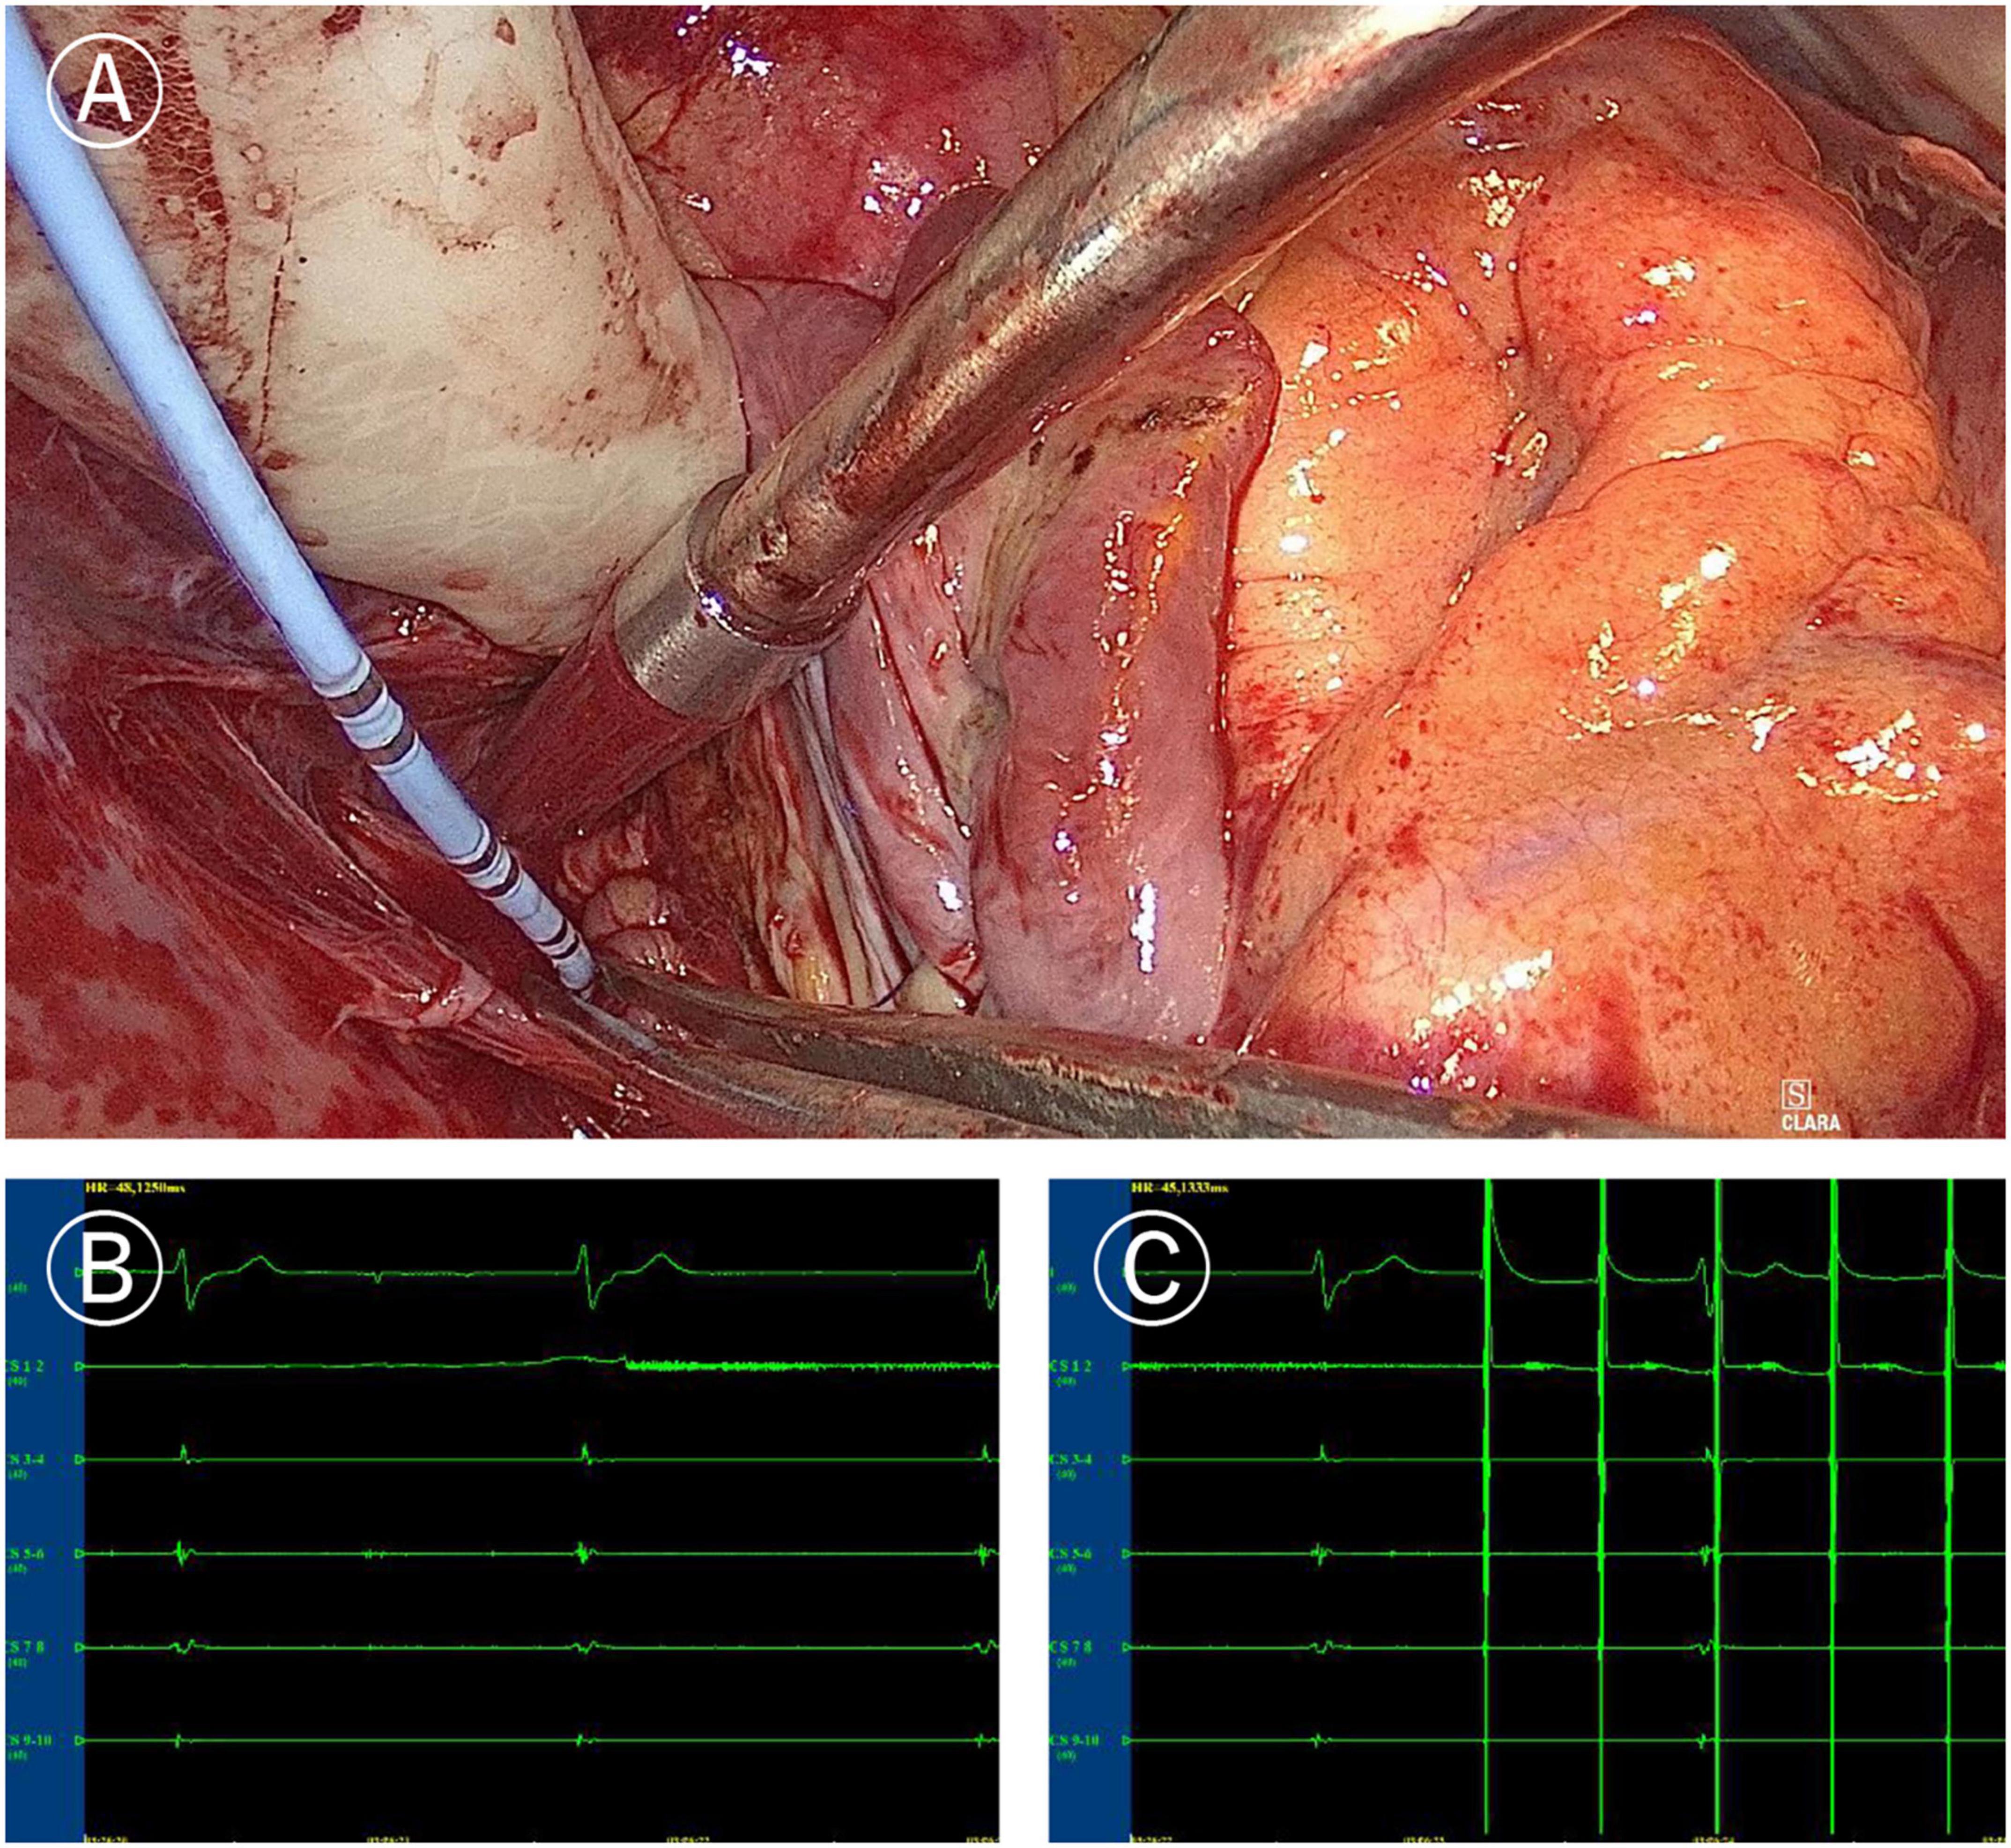

In the Electrophysio-Maze group, all patients underwent AF induction before and after the Cox-Maze IV procedure (Figure 1). The induction was performed with cannulization but without cardiopulmonary bypass, making the conditions consistent as much as possible. AF was induced in 88.1% (37/42) of all patients before Cox-Maze IV and was induced in 14.3% (6/42) of all patients after the Cox-Maze IV procedure. The bidirectional electrical isolation of the mitral annular isthmus ablation line (Figure 2), “box” ablation lines (Figure 3), and tricuspid annular ablation line (Figure 4) was successfully mapped in each patient. The rate of incomplete bidirectional electrical isolation of “box” ablation lines immediately after Cox-Maze IV was zero (the rate of complete bidirectional conduction block of “box” ablation lines immediately after Cox-Maze IV was 100%), and the rate of incomplete bidirectional electrical isolation of mitral isthmus ablation lines or tricuspid annulus ablation lines was 23.8% (10/42), wherein the rate of incomplete bidirectional electrical isolation of both mitral isthmus and tricuspid annulus ablation line was 7.14% (3/42), the rate of incomplete bi-directional electrical isolation of single mitral isthmus ablation line was 7.14% (3/42), and the rate of incomplete bidirectional electrical isolation of single tricuspid annulus ablation line was 9.52% (4/42). In two cases of incomplete bidirectional electrical isolation in single tricuspid annulus ablation line, complementary ablation was performed, and then electrophysiological mapping was performed again to ensure that the subsequent electrophysiological mapping confirmed the final complete bidirectional electrical isolation. The final incomplete bidirectional electrical isolation rate of mitral isthmus or tricuspid annulus ablation line was 19.0% (8/42). The incomplete bidirectional electrical isolation rate of ablation lines was correlated with AF inducibility immediately after Cox-Maze IV procedure but not with AF inducibility before Cox-Maze IV (Table 3).

Figure 3. Mapping of left atrial “box” lesion. (A) Coronary sinus catheter mapping of left atrial “box” lesion. (B) Inner-box polar could not sense the outer potential under sinus rhythm. (C) Pacing of inner-box polar could not capture or disturb the sinus rhythm of the outer atrium.